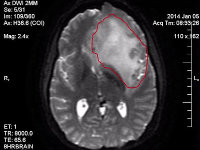

brain cancer imageNoni was diagnosed with terminal brain cancer. Her mind — the centre of everything — began slipping away. Treatments failed. Over 14 months, we watched her disappear.